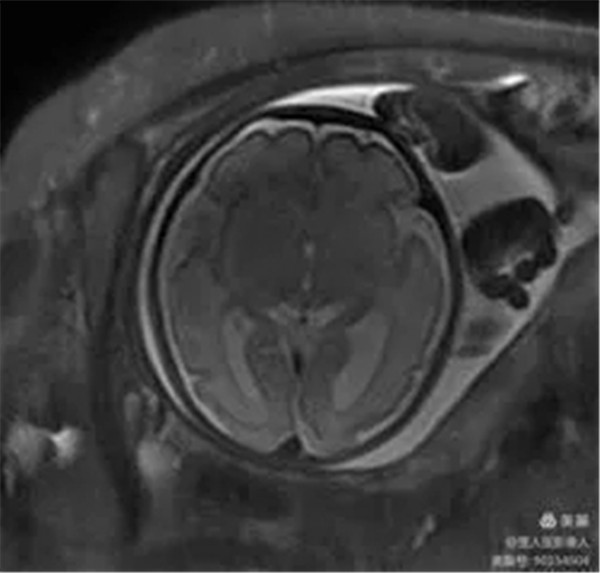

2、胎儿颅脑磁共振成像

病例12:评估胎儿颅脑发育情况。

图5,轴位fs-T2WI-显示颅脑

图8,轴位T2WI-显示颅脑